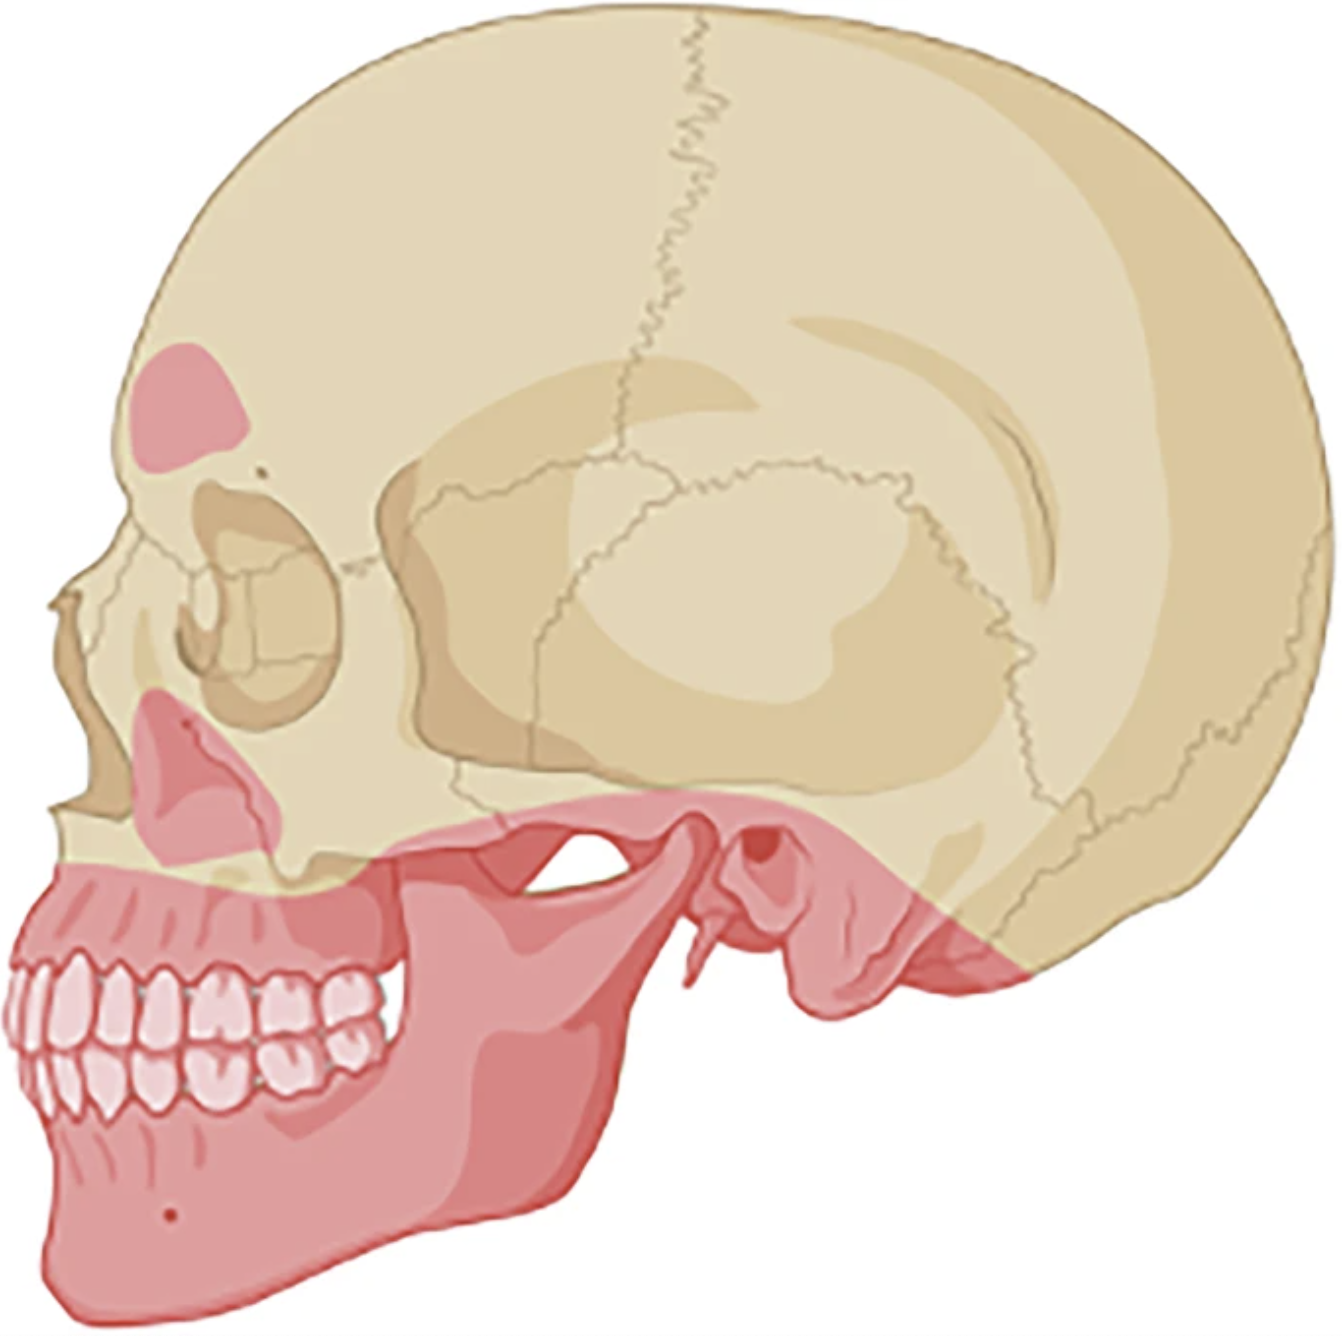

The authors of a recent study used computed tomography (CT) scans to examine 15 Viking Age skulls recovered from the Varnhem cemetery in Sweden. After consulting dentists and facial pathologists, they found that many of those ancient humans likely suffered greatly from a range of infections and other tooth-related issues.